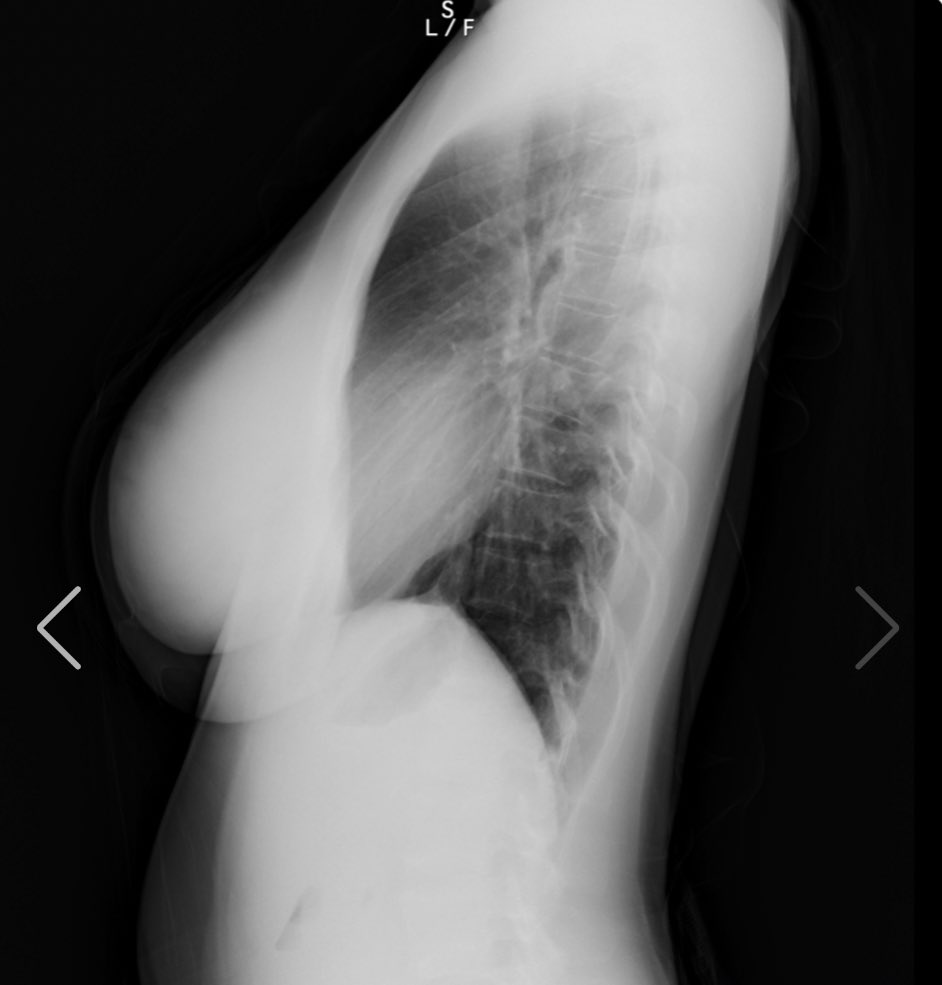

人気爆乳グラドル天木じゅん、スケスケの丸見えオッパイを解禁し偽乳疑惑を払拭するww グラビア天木じゅん 2021年8月21日 7:07 17コメント Tweet ※当サイトはアフィリエイト広告を利用しています 似ている人気記事 バスト約100cm美少女ちとせよしの、紐タイプのハイレグ衣装でえちえちなバニーコスプレに挑戦しほぼ裸の格好にww 長身×巨乳×美脚の現役バニーガール 蜂羽レム、店から黙って拝借したバニーコスを着てノリノリAVデビューwww 名門ミスコン「ミスマガジン」2021~2023の3世代・18名が大集合、個性溢れるビキニ姿を見せてるww ertkな名無し レントゲンでもわかるエロいおっぱい 私の胸部レントゲン!www正面から見た写真の右の胸の黒いのは胃泡だよ安心してね裸を通り越して私の骨と脂肪を見れたあなたには幸運が訪れると信じてます❤️(私の胸は遺伝です)w#1mmでもいいなと思ったらRT #胸部レントゲン #人間ドック pic.twitter.com/OmgFNaRvui— 天木じゅん (@jun_amaki) August 18, 2021 ertkな名無し 医者になればオッパイのレントゲン見放題か・・ ertkな名無し これは本物 小池栄子様♀️♀️♀️#1mmでもいいなと思ったらRT #天木TikTok pic.twitter.com/8vkmhu0LD2— 天木じゅん (@jun_amaki) August 9, 2021 ertkな名無し 綺麗な肺ですね まさにフルヌード 撮影頑張ってきます♥︎#1mmでもいいなと思ったらRT pic.twitter.com/BO6j7hkZqW— 天木じゅん (@jun_amaki) August 10, 2021 9th DVD『じゅんちゃん♡』絶賛予約受付中https://t.co/F94nYpmxMOオフショットだよっっ#1mmでもいいなと思ったらRT pic.twitter.com/76ljB26SHC— 天木じゅん (@jun_amaki) August 15, 2021 天木じゅん 最新作 https://www.dmm.com/mono/dvd/-/detail/=/cid=n_701tsds42550tk/ サンプル再生 こちらの「サンプル再生」でも見れます 天木じゅんの関連記事:アンテナからエロチカ記事へのリンク 天木じゅんが初DVDでIカップの爆乳使ってパイズリwww 枕営業が話題の仮面女子が冠番組でスク水で入浴百合プレイwww 仮面女子天木じゅんのHカップ爆乳使った隠し芸が卑猥すぎwwwwww コメント 通りすがりの紳士:2021/8/21 7:34 アッハイ 通りすがりの紳士:2021/8/21 8:35 おっぱい 通りすがりの紳士:2021/8/21 8:47 問題は乳じゃないんだっていい加減気付けよ。 通りすがりの紳士:2021/8/21 8:50 天木じゅんがどうとかいうわけじゃなくレントゲンなんて何の意味もないぞ シリコンバッグじゃなくて脂肪注入じゃレントゲンでわからんからな 昔はペチャパイだった、ほしのあきが偽乳疑惑かわすためにTVの企画ですでにやってる。 通りすがりの紳士:2021/8/21 10:24 ぶち込みたいわ 通りすがりの紳士:2021/8/21 10:41 俺はずっと信じてたぜ!じゅんちゃんの唯一の存在意義は乳袋なのにそれで嘘つくわけないよ! 通りすがりの紳士:2021/8/21 11:04 >>6 拾い物って言葉知ってる?残念だけど偽乳って周りが認識してしまったらそれはもう偽乳なの 同じカップ数なら柳瀬さきのが至高ですよ? 通りすがりの紳士:2021/8/21 11:21 流石にこれが偽乳と言うのは無理があるよなw 通りすがりの紳士:2021/8/21 11:26 ぶち込みたいわ、 通りすがりの紳士:2021/8/21 11:33 >>8 お前の思考に無理がある() 通りすがりの紳士:2021/8/21 16:36 最近は脂肪吸引したもの以外にも、ヒアルロン酸をうつ豊胸もあります。 効果の時間は脂肪吸引より短いですが、メスを使わないので安全ですし 写真集を出す前とかに少しボリュームをアップするのに効果があります。 通りすがりの紳士:2021/8/21 18:43 顔がねぇ 通りすがりの紳士:2021/8/21 19:08 ※12 キモメンのお前が言える顔じゃねえだろ 通りすがりの紳士:2021/8/21 19:56 ていうか今回はアイドル学園公式サイトではサンプル画像無いのね…ひそかに楽しみにしてたのに… 通りすがりの紳士:2021/8/21 20:19 高濃度乳腺 通りすがりの紳士:2021/8/21 21:16 ※13 一般人とアイドル比べてどうすんのw 通りすがりの紳士:2021/8/22 13:27 偽乳じゃない証明ならレントゲンじゃなくブラックライト照らせば一発でわかるのにw 静止画だと解りづらいが動画だと顔が不自然なのが解る。 コメント Δ 日本語が含まれない投稿は無視されますのでご注意ください。(スパム対策)

天木じゅんがどうとかいうわけじゃなくレントゲンなんて何の意味もないぞ

シリコンバッグじゃなくて脂肪注入じゃレントゲンでわからんからな